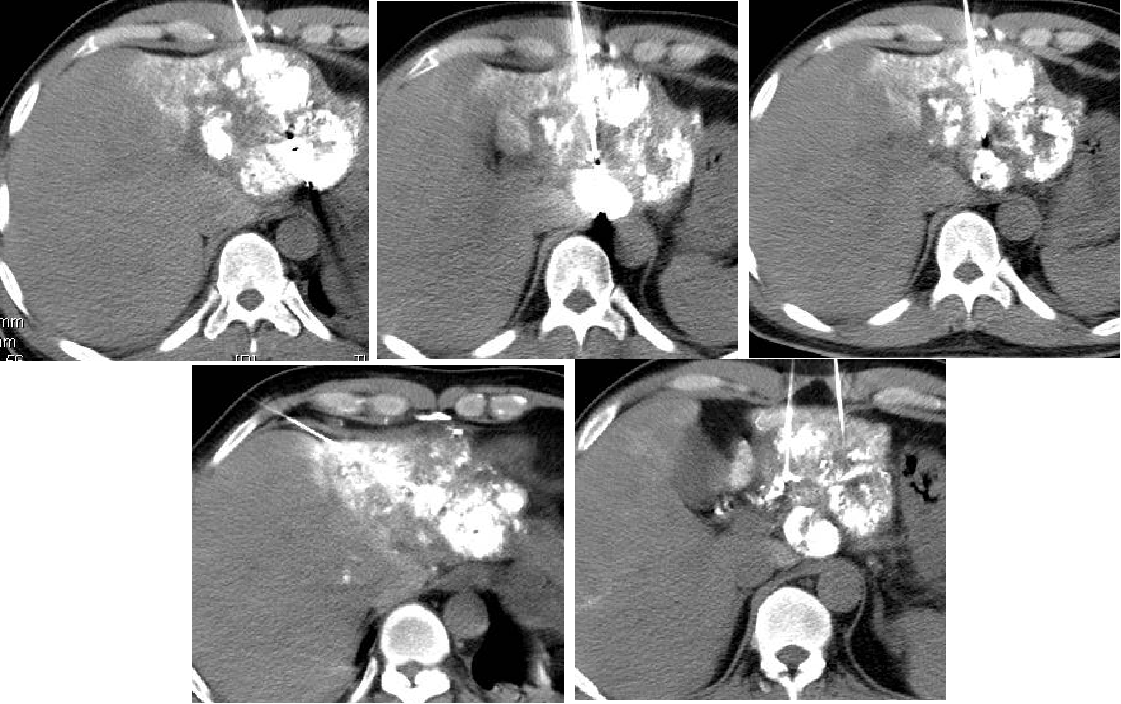

2011-01-06我院上腹部CT:

肝左叶巨块型肝癌(13.8cm×9.1cm),伴肝右后叶子灶,门静脉左支、肝左静脉及下腔静脉内癌栓。

2011-01-07 对肝左叶病灶行第1次TACE术(碘化油18ml,THP 46mg)

2011-02-12复查CT示:肝左叶碘油散在沉积,病灶大部分仍有活性,肝右后叶病灶未见碘油沉积;门静脉癌栓较前进展,累及主干及右支;肝左静脉及下腔静脉内癌栓无明显变化。AFP:26802 ng/ml。

2011-02-16行第2次TACE术(碘化油15ml,THP 45mg)

2011-04-20复查CT示:肝左叶病灶较前缩小,肝右叶病灶见碘油致密沉积;门脉癌栓左支较前缩小,右支癌栓消失;下腔静脉、肝左静脉癌栓消失。AFP:4983 ng/ml。

2011-06-09(第二次TACE后4个月)复查肝脏CT示:肝左叶病灶继续缩小,但仍有肿瘤残留。AFP:8137 ng/ml(较上次复查明显升高)。

2011-06-14行第3次TACE术(碘化油15ml,THP 35mg)

2011-08-15复查CT示:肝左叶病灶大小较前相仿,仍有肿瘤残留。